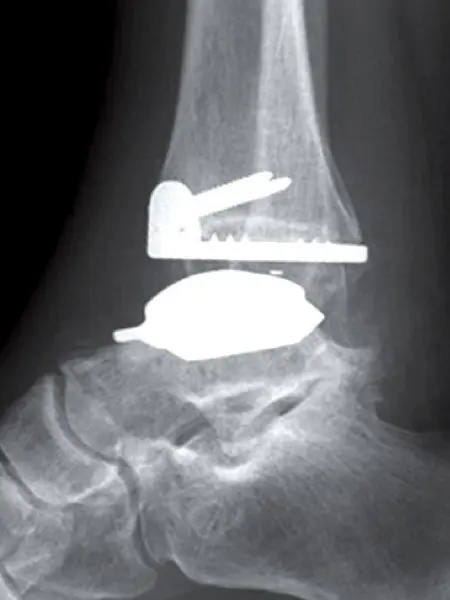

Proteza typu Hintegra stawu skokowego – widok z boku

Proteza stawu skokowego typu Hintegra polega na wszczepieniu specjalnych implantów w miejsce uszkodzonej powierzchni stawowej. Dzięki temu Pacjent odzyskuje pełny zakres ruchu w stawie skokowym i może nie tylko normalnie chodzić, ale nawet biegać.